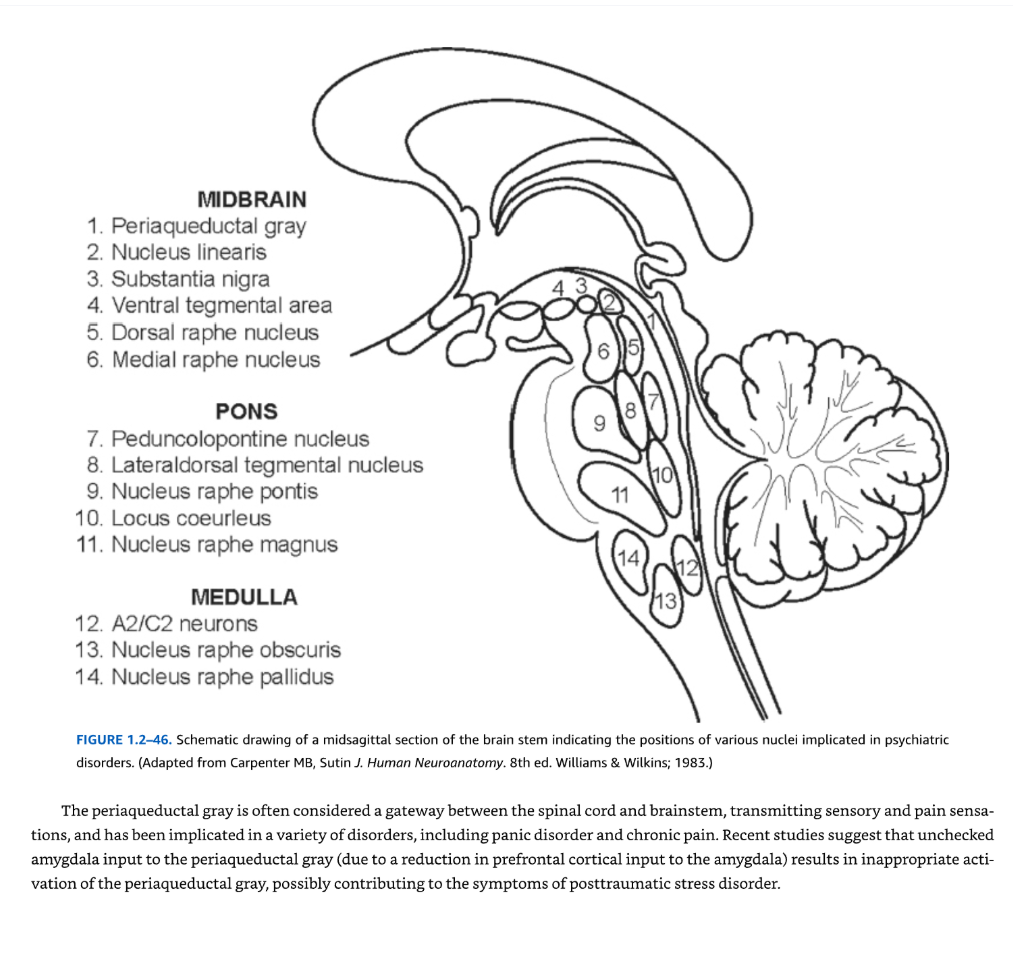

脳幹 前述のように、脳幹は吻側から尾側に向かって中脳、橋、延髄の3つの区分に分けられる(図1.2-46)。脳幹は多面的な構造であり、一般的に自律神経機能と感覚処理を司ると考えられている。脳幹の網様体核群は総じて網様体を構成し、これには脳幹のより緊密で名前の付いた核の間に散在するすべてのニューロンが含まれる。多数の研究により、脳幹内に埋め込まれた核のいくつかが、精神疾患でしばしば障害される情緒的・認知的機能において重要な役割を果たすことが明らかになっている。

中脳 中脳内では、黒質と腹側被蓋野(図1.2-26、1.2-46、1.2-47参照)が精神障害に対して特に重要である。これらの領域のニューロンはドーパミンの主要な産生源だからである。これらの結合とそれらが精神障害に与える影響については、前の章(大脳基底核/主要構造/黒質)で概説されている。

中脳内のその他の注目すべき核には、歴史的に情動の調節と痛みの体験に関連してきた中脳水道周囲灰白質がある(図1.2-46参照)。中脳水道周囲灰白質は大脳水道を取り囲み(図1.2-47参照)、吻側から尾側に配向した4つの柱から構成される:背内側中脳水道周囲灰白質、背外側中脳水道周囲灰白質、外側中脳水道周囲灰白質、腹外側中脳水道周囲灰白質(図1.2-47参照)。2つの背側柱と2つの腹側柱はしばしば組み合わされて、それぞれ背側中脳水道周囲灰白質と腹側中脳水道周囲灰白質を形成する。背側中脳水道周囲灰白質は扁桃体、腹内側視床下部、内側前頭前皮質、およびすべての感覚系から神経支配を受ける。背側中脳水道周囲灰白質は交感神経系を神経支配し、自律神経活動の増加を伴う闘争/逃走反応およびその他の能動的対処反応を促進すると考えられている。腹側中脳水道周囲灰白質は前島皮質と背内側前頭前皮質から標的とされ、副交感神経系を神経支配する。腹側中脳水道周囲灰白質は受動的対処機制を仲介すると考えられている。

中脳

- 中脳水道周囲灰白質

- 線状核

- 黒質

- 腹側被蓋野

- 背側縫線核 6.内側縫線核

橋 7. 脚橋被蓋核 8. 外側背側被蓋核 9. 橋縫線核 10. 青斑核 11. 大縫線核

延髄 12. A2/C2ニューロン 13. 暗縫線核 14. 淡縫線核

図1.2-46. 精神障害に関与する様々な核の位置を示す脳幹の正中矢状断面の模式図(Carpenter MB, Sutin J. Human Neuroanatomy. 8th ed. Williams & Wilkins; 1983より改変)

中脳水道周囲灰白質はしばしば脊髄と脳幹の間の関門と考えられ、感覚と疼痛感覚を伝達し、パニック障害や慢性疼痛を含む様々な障害に関与している。最近の研究では、扁桃体から中脳水道周囲灰白質への抑制されない入力(扁桃体への前頭前皮質からの入力の減少による)が中脳水道周囲灰白質の不適切な活性化をもたらし、心的外傷後ストレス障害の症状に寄与している可能性があることが示唆されている。